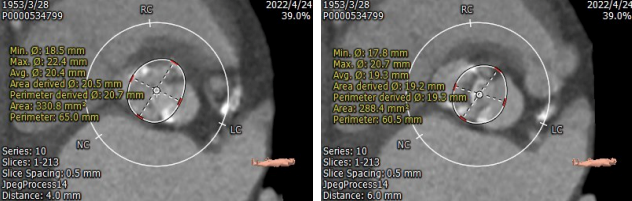

环上4mm/6mm预估可推开空间周长65.0m/60.5mm

二叶式主动脉,Type0型。瓣叶轻度钙化,钙化主要分布于瓣叶、瓣叶交界,瓣环周长64.8mm,平均径20.3mm, LVOT周长64.8mm,平均径19.8mm,环上4mm/6mm预估可推开空间周长65.0m/60.5mm;入路两侧血管分叉高度可,内径可,无迂曲。